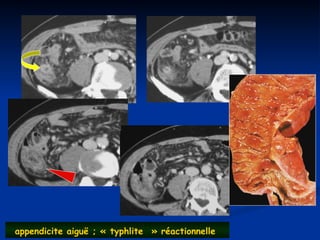

appendicite aiguë ; « typhlite » réactionnelle

appendicite aiguë ;« typhlite » réactionnelle